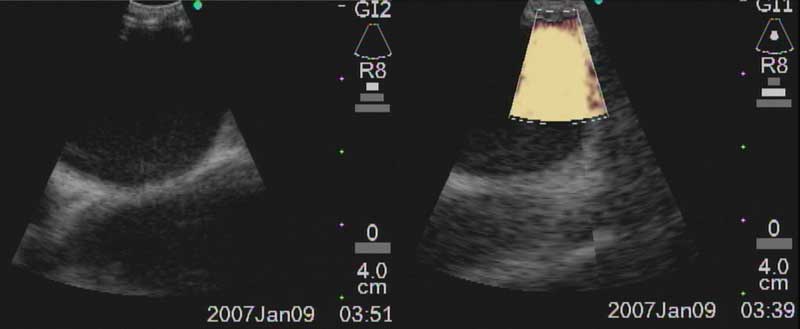

The easiest place to start ultrasound imaging is generally the right main bronchus and subcarinal areas. Pass the scope to the right side of the carina with the probe facing anteriorly and apply to the anterior wall of the RMB. This will bring into view the right main pulmonary artery. Vascular structures appear hypoechoic and pulsatile, and are usually readily discernable without using the color Doppler. If doubt persists flow within can be confirmed by switching to the Doppler overlay (B/CPD; Figures 5 and 6). Turn the scope 90 degrees counter-clockwise. This allows visualization of the subcarinal area from the right side. By moving the scope in and out the level 7 subcarinal node can usually be identified. If not, repeat this procedure in the LMB turning the scope 90 degrees clockwise instead. Once the subcarinal nodes are visualized it is relatively easy to identify other landmarks, by correlating anatomical location with the ultrasound image. It is useful to attempt to map out all nodes that you wish to biopsy first, before needle tract bleeding confounds the fiber optic image. The size of the node can be measured by freezing the US image [Freeze] and using the [Measure/Select] button and cursor scroll ball (Figures 5 and 7).

Figure 6a: Ultrasound image of R main pulmonary artery with (right) and without (left) color Doppler.